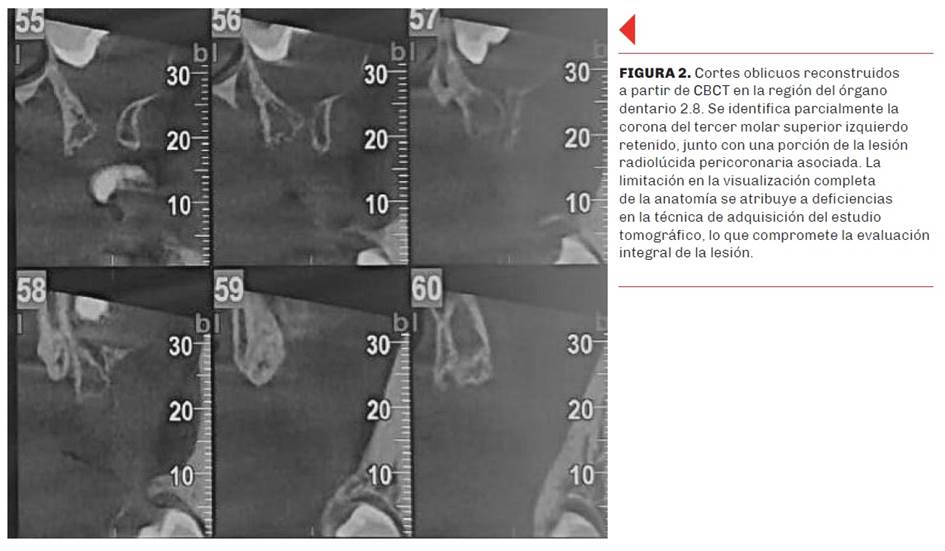

Se presenta el caso de una paciente de sexo femenino, de 13 años de edad, derivada al Servicio de Diagnóstico por Imágenes de la Facultad de Odontología de la Universidad de Buenos Aires por su odontólogo tratante, con el objetivo de evaluar la presencia de terceros molares retenidos. En la radiografía panorámica inicial se observó la retención de los cuatro terceros molares, obtenida en un equipo Planmeca ProMax® 2D S2, de 66–70 kV, 8–10 mA, y un tiempo de exposición de 14 segundos. En relación con la pieza dentaria 2.8, se evidenció una imagen unilocular radiolúcida bien delimitada, de aspecto osteolítico, que rodeaba la corona dental y presentaba un halo radiopaco periférico compatible con una cortical reactiva, siendo compatible con un diagnóstico presuntivo de quiste dentígero (Figura1). Dicha pieza se hallaba en posición ectópica, presumiblemente como consecuencia del efecto expansivo de la lesión.

La paciente se encontraba asintomática, por lo que el hallazgo fue incidental y radiográfico. Dada la limitación inherente a las imágenes bidimensionales obtenidas por ortopantomografía —como la superposición de estructuras y la falta de información en profundidad— se indicó la realización de una tomografía computarizada de haz cónico (CBCT), la cual fue efectuada en otro centro. La imagen volumétrica permite una mejor caracterización de la lesión. La CBCT es una herramienta complementaria invaluable en el diagnóstico y planificación quirúrgica. Proporciona imágenes tridimensionales detalladas que permiten una evaluación precisa de la extensión de la lesión, la relación con estructuras anatómicas adyacentes y la planificación de abordajes quirúrgicos menos invasivos.